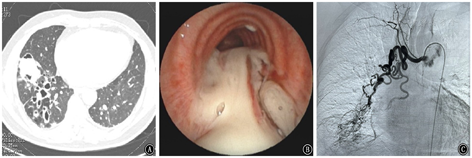

咯血是呼吸系统的危急重症,与其他部位出血不同,少量的血凝块即可能堵塞气道从而危及患者生命,病死率超过70%[39]。一次咯血量超过200 ml或24 h咯血量超过500 ml为大咯血[40]。大咯血最严重的并发症是窒息,最重要的处理措施是尽早畅通气道及立即阻断出血[19]。SAE联合呼吸内镜介入技术在大咯血的诊治中具有很好的临床作用:对于发生窒息性大咯血,且氧饱和度<90 mmHg(1 mmHg=0.133 kPa)时,患者生命体征不稳定,立即行血管介入止血存在风险,此时呼吸内镜联合肺血管介入诊疗至关重要。首先快速气管插管,建立有效人工气道,即刻使用支气管镜快速清除气道内血凝块畅通气道,还可以明确出血部位并局部止血,必要时放置球囊压迫止血,保护健侧肺,并为血管介入诊疗争取时间。在生命体征稳定后,即刻至导管室行SAE进行病理血管的栓塞进行止血治疗,在某些复杂的病变如毁损肺、血管非常纤细、异位支气管动脉或非支气管性体动脉参与病灶供血等情况下,容易出现病理血管遗漏,在行SAE术中或术后再同台行支气管镜检查,有助于寻找目标血管,可提高手术成功率,减少复发率。笔者单位的研究[41]显示:153例因支气管扩张症导致的咯血患者术后2年仅有16例复发,复发率为10.5%,分析原因考虑运用了肺血管介入和呼吸内镜介入联合治疗即"双介入"治疗手段。具体流程见图1。病例1:女性患者,86岁,因"间断咯血1月余"入院。患者有大咯血窒息,总出血量约1 000 ml。联合治疗情况见图2。

注:DSA为数字减影血管造影;SAE为选择性体动脉栓塞术